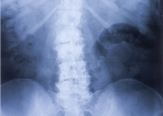

Što je skolioza?

Najkraće rečeno skolioza je postranično iskrivljenje kralježnice. Često će rezultirati S ili C oblikom kralježnice. Krivulje se obično manifestiraju u torakalnom i/ili lumbalnom dijelu kralježnice. Skolioza može biti prisutna od rođenja ili se razvije vremenom kao posljedica nekih drugih stanja poput cerebralne paralize ili mišićnih distrofija. Skolioza se može razviti uslijed mišićne neravnoteže uzrokovanom nekom fizičkom traumom, odnosno ozljedom. Recimo nesrećom ili stalnim ponavljanjem određenih pokreta gdje se forsira jedna strana tijela, poput kuglanja, tenisa ili bacačkih sportova. Kod djece se može javiti skolioza uslijed nošenja (pre)teških torbi na jednom ramenu.

Skolioza u nekim slučajevima nije potpuno očita. Možete napraviti test da vam netko s dva prsta s obje strane kralježnice prođe uzduž, ostavljajući dva crvena traga. Skolioza će često biti vidljiva u tim tragovima, odnosno vidjeti će se iskrivljenje.